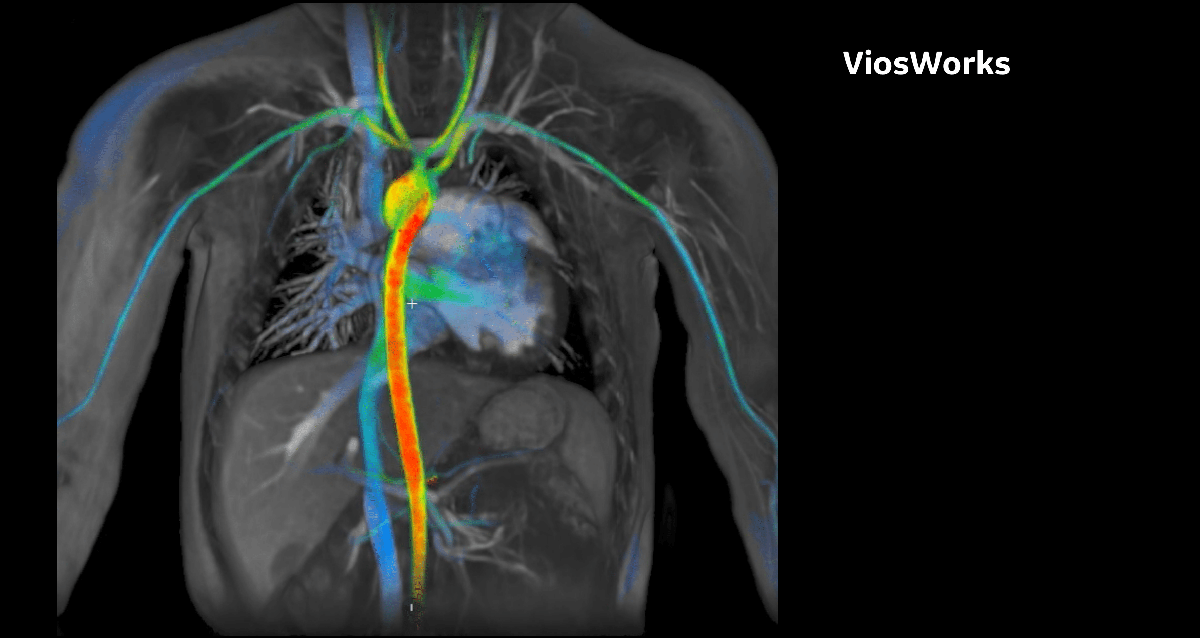

ViosWorks

Уменьшает трудоемкость и издержки визуализации сердца. Впервые все 7 пространств визуализации могут быть одновременно отображены за одно сканирование, меньше, чем за 10 минут.